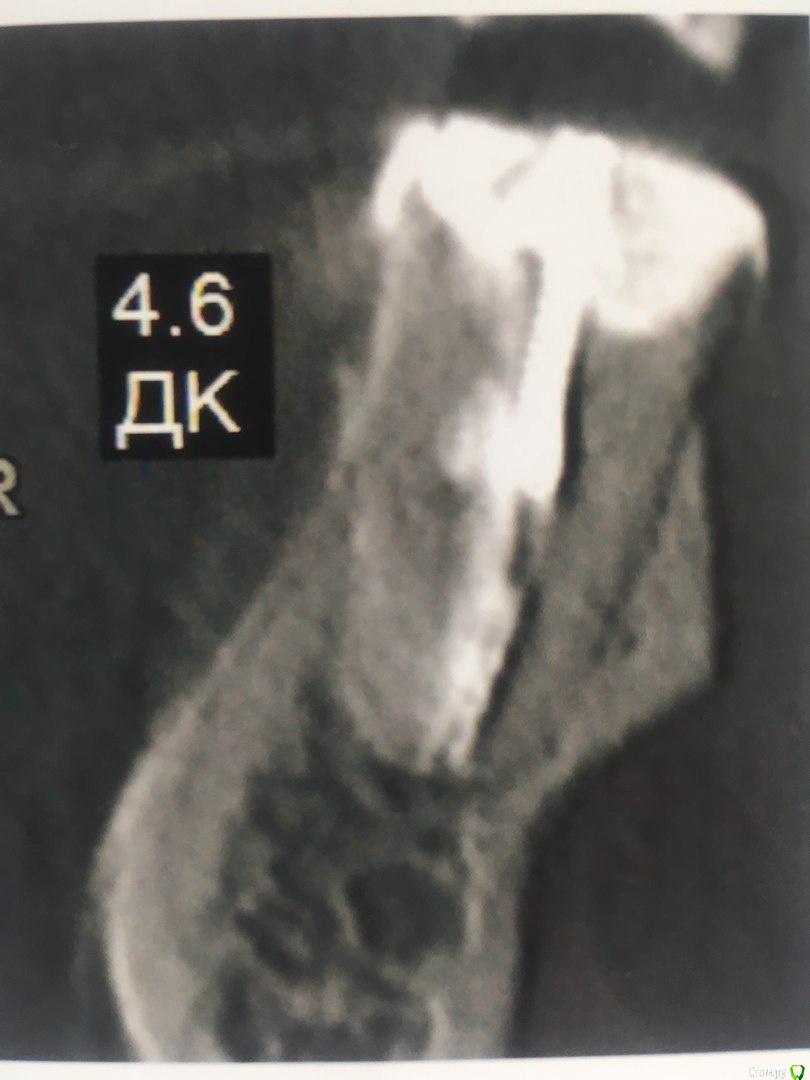

Здравствуйте. Прошу совета у специалистов. Удалять или лечить нижнюю 6-ку?

И вот уже несколько лет нижняя 6-ка периодически ноет (особенно если остыть),каждый год ходила  к одному хирургу,готовясь  уже удалить этот источник неприятных ощущений, но каждый раз врач делая р.снимок говорил все нормально.

Коронковой части у зуба практически нет,только корень, поставлен штиф  и на него пломба в виде коронки зуба.

В течении  года от зуба опустилась десна и там проглядывается прозрачно-черный корень и очень быстро на 5 и 4-ки обазовались черные пятна.  Сделала КТ. Теперь стоит вопрос долгое  лечение или удаление.Врач говорит все будет видно при вскрытии. Если лечение то долгое и без гарантий.   Мне кажется от корня там мало что осталось,судя по цвету и по тому как быстро испортились рядом стоящие зубы. Может проще не лечить,установить имплант?

Правда один врач сказал,что то вроде убыли костной ткани и имплант удержать будет не чем,кроме того сужение верхней челюсти, рецессия десны и стирание в пришеечной области из за прикуса. В заключении кт -пародонтопатия легкой степени тяжести.

Добрый вечер!  Благодарю за ответ. Побывала у другого врача. Мнения разошлись. Второй доктор сказал 4,6  удаляем, а верхний 2,6 лечим.Первый же доктор сказал наоборот. Можно спросить еще Ваше мнение по 2,6 и 2,5 зубам?)

С каналами можно решить все проблемы. А вот с тем что тканей зуба очень мало,  можно оценить прогноз только после вскрытия.